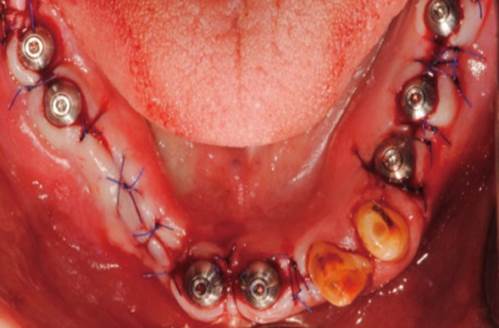

Clinical case: Full-mouth implants for mandibular & maxilla - restored using mixed prostheses

- Courtesy of Dr. Hyun Jun Kim, Korea -

Keywords

AnyRidge, full-mouth implants, mandibular, maxilla, edentulous, full mouth rehabilitation, Octa abutment, long-term clinical case, biological stability, Dr. Hyung Jun Kim

Products:

AnyRidge implant system